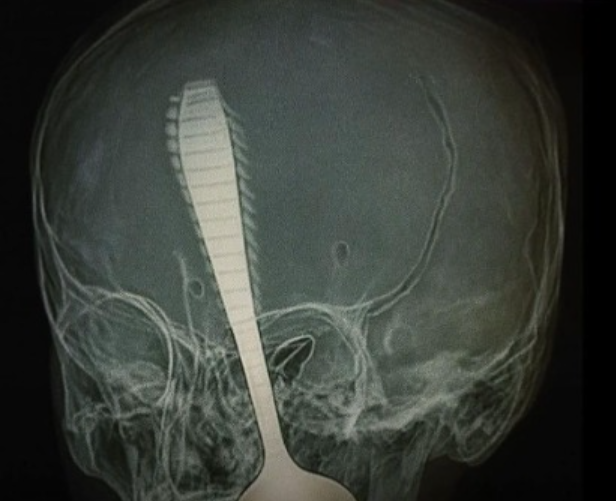

Uma menina de apenas 1 ano e 3 meses perdeu um dos olhos após sofrer um grave acidente doméstico envolvendo um objeto considerado comum no dia a dia: uma colher. O caso, que abalou a família e gerou forte comoção, reforça os riscos silenciosos presentes dentro de casa, especialmente para crianças pequenas que ainda estão em fase de desenvolvimento motor.

Segundo relatos dos familiares, a criança corria pelo ambiente segurando uma colherinha quando se desequilibrou e caiu. O impacto provocou um ferimento profundo na região do rosto, atingindo diretamente o olho. O socorro foi imediato, e a menina foi levada às pressas para atendimento médico especializado. Apesar da gravidade da lesão e da perda ocular, o quadro clínico geral da criança é considerado estável.

O reflexo natural das crianças ao cair, somado à falta de coordenação motora plena, aumenta a chance de que objetos atinjam regiões sensíveis do corpo, como olhos, boca e pescoço. Lesões oculares, em especial, podem causar danos irreversíveis em questão de segundos, como ocorreu neste caso.

Dados da área da saúde indicam que quedas são a principal causa de atendimentos de emergência envolvendo crianças pequenas. Quando associadas a objetos nas mãos, o potencial de gravidade aumenta consideravelmente, podendo resultar em perfurações, traumatismos faciais e danos neurológicos.